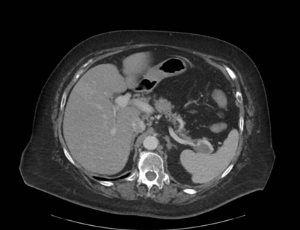

The term paraduodenal pancreatitis and groove pancreatitis are today used interchangeably, with all conditions having similar manifestations; they refer to an uncommon and still under-recognized form of recurrent or chronic pancreatitis that affects the so-called groove. The groove represents the potential space between the head of the pancreas, medially and the second part of the duodenum, laterally. It is bordered by the duodenal bulb and the third part of the duodenum in the superior and posteroinferior aspects, respectively.